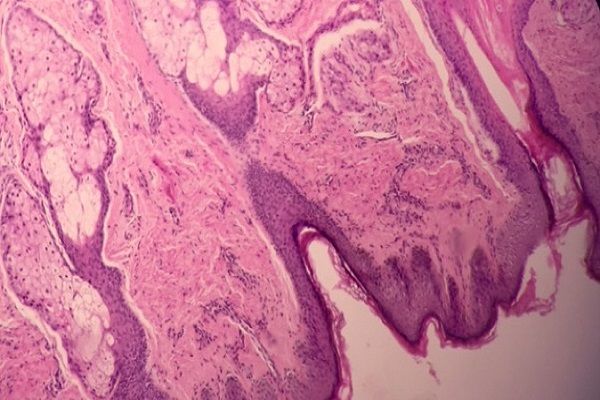

Question 3

Question

Label this image

Image:

6eeff475-4763-457e-a546-bc0f8ac946e8 (image/jpeg)

Answer

Embryonic Tooth